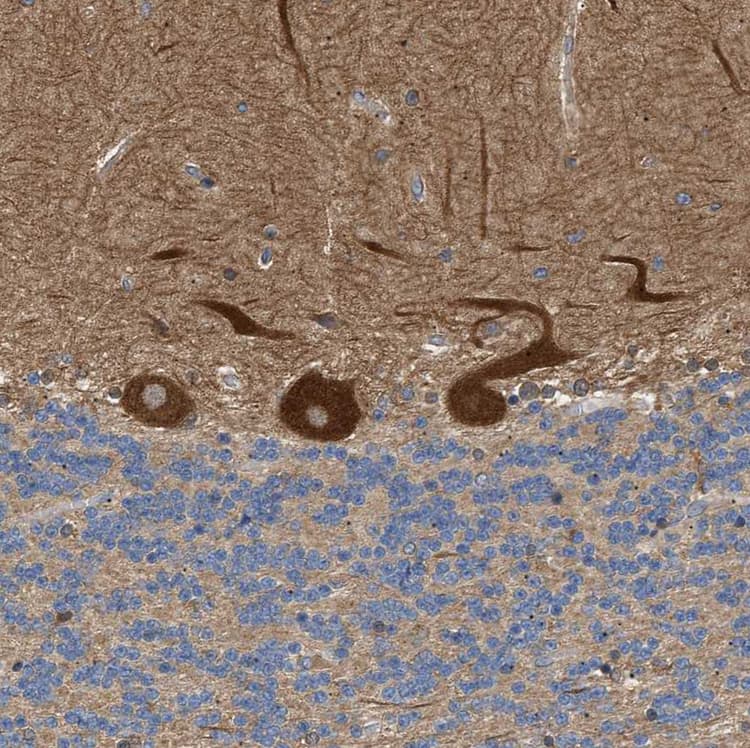

Rabbit Polyclonal PPM1B antibody. Suitable for IHC-P, WB, ICC/IF and reacts with Human samples. Cited in 1 publication. Immunogen corresponding to Recombinant Fragment Protein within Human Protein phosphatase 1B aa 350 to C-terminus.

Applications ICC/IF, IHC-P, WB

Species Reactivity Human